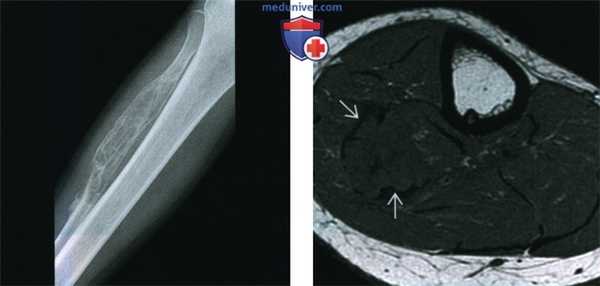

(Слева) Рентгенография в ПЗ проекции: умеренно агрессивный, вспученный литический диафизарный очаг с псевдотрабекуляцией и патологическим переломом в дистальном отделе. Данные признаки не специфичны. Двумя наиболее вероятными диагнозами являются неоссифицирующая фиброма и десмопластическая фиброма.

(Справа) МРТ, аксиальная проекция, режим Т1: внутрикостный очаг у этого же пациента В, характеризующийся сигналом, интенсивность которого немногим ниже сопряженной мышцы. Визуализируется выраженная вспученность малоберцовой кости. Такие признаки неспецифичны, однако сигнал очень низкой интенсивности предполагает наличие фиброзного очага.

• Режим Т1: низкая интенсивность сигнала (изо- или гипоинтен-сивный по отношению к мышце)

• Последовательности, чувствительные к жидкости (с подавлением или без подавления сигнала от жира): изо- или гипоинтенсивный сигнал по отношению к мышце:

о Сигнал низкой интенсивности в режиме Т2 охватывает не менее 50% очага

о Сигнал низкой интенсивности в режиме Т2 является наиболее значимым дифференциально-диагностическим признаком

о Может искажаться на фоне отека и кровоизлияния в зоне патологического перелома

• Контрастное усиление: неоднородное накопление контраста

(Слева) МРТ, аксиальная проекция, режим Т2, с подавлением сигнала от жира: у этого же пациента определяется область преимущественно низкоинтенсивного сигнала, окруженная зоной умеренно выраженного отека. Низкоинтенсивный сигнал занимает большую часть патологического очага. Десмопластическая фиброма является внутрикостной формой фиброматоза или мягкотканного десмоида. Такое новообразование встречается редко, его наличие можно предполагать при умеренно агрессивном костном очаге, большая часть которого имеет сигнал низкой интенсивности в режиме Т2.

(Справа) МРТ, сагиттальная проекция, режим Т1, с подавлением сигнала от жира и контрастированием, этот же пациент: очаге контрастным усилением.